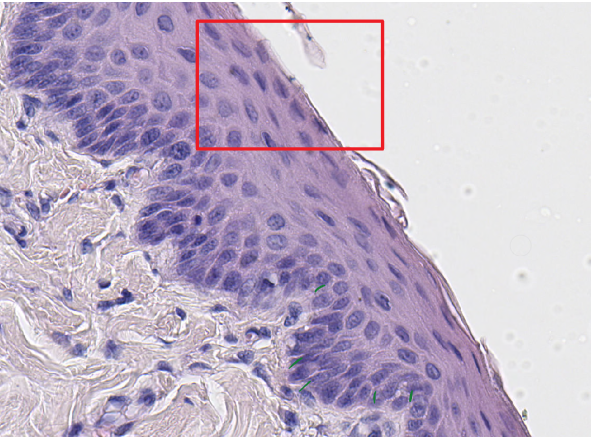

Identify this structure:

non-keratinized stratified squamous epithelium

Q

epidermal peg

dermal papilla

What is the functional significance of interdigitating?

for structure and water absorption